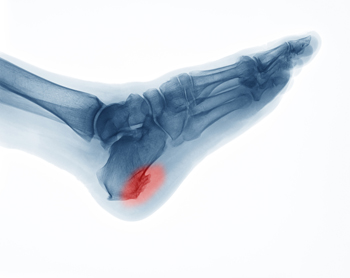

How Did I Get a Heel Spur?

A spur is a bony growth that may develop due to repetitive irritation or stress. As its name suggests, a heel spur develops on the heel bone or calcaneus. More specifically, it typically forms in one of two places on the heel bone. An inferior calcaneal spur forms underneath the heel bone and is associated with plantar fasciitis, a common ligament injury in the foot. A posterior calcaneal spur forms on the back of the heel bone and is associated with Achilles tendonitis. Heel spurs can be asymptomatic or cause sharp pain, dull aches, stiffness, and numbness in the affected heel. Corns and calluses also often form over the affected area. If you have painful heels, please see a podiatrist for a diagnosis and treatment.

Heels Spurs

Heel spurs are formed by calcium deposits on the back of the foot where the heel is. This can also be caused by small fragments of bone breaking off one section of the foot, attaching onto the back of the foot. Heel spurs can also be bone growth on the back of the foot and may grow in the direction of the arch of the foot.

Older individuals usually suffer from heel spurs and pain sometimes intensifies with age. One of the main condition's spurs are related to is plantar fasciitis.

Pain

The pain associated with spurs is often because of weight placed on the feet. When someone is walking, their entire weight is concentrated on the feet. Bone spurs then have the tendency to affect other bones and tissues around the foot. As the pain continues, the feet will become tender and sensitive over time.

Treatments

There are many ways to treat heel spurs. If one is suffering from heel spurs in conjunction with pain, there are several methods for healing. Medication, surgery, and herbal care are some options.